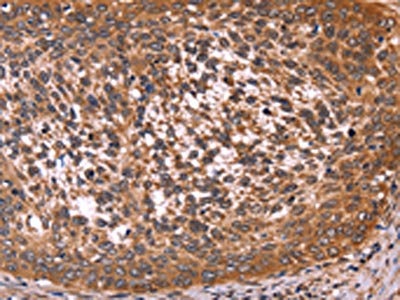

The image on the left is immunohistochemistry of paraffin-embedded Human colon cancer tissue using CSB-PA965050(CCDC106 Antibody) at dilution 1/50, on the right is treated with fusion protein. (Original magnification: ×200)

The image on the left is immunohistochemistry of paraffin-embedded Human cervical cancer tissue using CSB-PA965050(CCDC106 Antibody) at dilution 1/50, on the right is treated with fusion protein. (Original magnification: ×200)